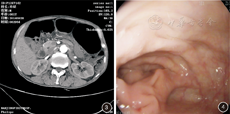

例2 患者男,81岁,因"反复便秘、腹胀十余年,腹泻伴大便失禁1个月余"入院。患者十余年来反复便秘、腹胀,1个月前出现腹泻伴大便失禁,无脓血便,无里急后重,不伴发热。入院查体无明显腹部体征。腹部CT示乙状结肠至升结肠明显扩张(图3)。血常规:WBC 3.05×109/L、N 36.1%、Hb 109 g/L、Plt 120×109/L;粪便常规正常、粪便培养阴性。肠镜示结肠肠腔明显扩张,结肠黏膜尚光滑,血管纹理尚清晰(图4),结肠活检未见明显异常,直肠下端正常黏膜处活检示肠壁神经节可见。予一般对症支持治疗,随访3年至今患者情况良好。诊断为"特发性巨结肠"。